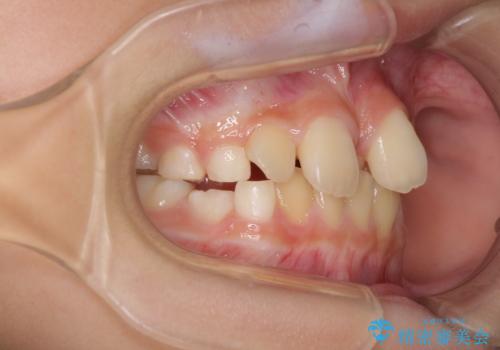

- 前歯の叢生を気にして来院された、小学校3年生女児の患者様です。

身長がやや低く、乳歯から永久歯への交換が少し遅い印象があったので、ワイヤー装置による1期矯正治療ではなく、乳歯も積極的に動かすことのできるインビザライン・ファーストにて治療を行うこととしました。

上顎前歯に過剰歯があったため、まずはその歯を抜歯し、傷が治癒したタイミングでインビザラインを発注することとしました。